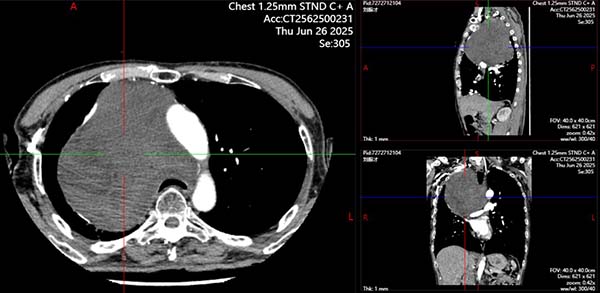

30 岁患者小陈因胸痛查出后纵隔 5×4 厘米肿物,辗转多家医院均束手无策。这个 “定时炸弹” 长在气管隆突下方、食管前方,不仅压迫左主支气管完全闭塞、左肺无法张开,同时肿物被左肺动脉主干和主动脉紧紧 “包裹”,常规左侧胸腔入路根本无法触及肿物,甚至术中左侧单肺通气都做不到——这意味着术中的氧合维持成了最先面对的巨大挑战。

刘志东团队联合多学科专家反复研判,最终决定在 ECMO(体外膜肺氧合,俗称 “人工肺”)支持下从右侧胸腔入路行肿物切除手术。2025 年 6 月 30 日,手术团队在 ECMO 护航下精准操作,避开层层大血管,成功完整切除纵隔肿物。术后患者在手术室顺利撤离 ECMO,经过科学治疗与护理,目前已康复出院。